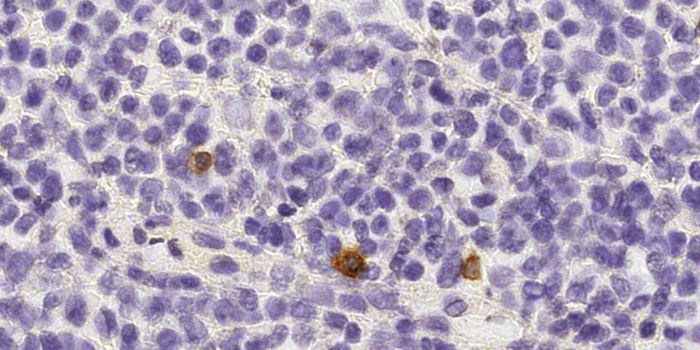

NOV 20, 2019ImmunologyManipulating the immune system’s population of natural killer cells could bolster therapies targeting cancer. A ne ...

JAN 23, 2018ImmunologyScientists propose extracting dendritic cells and priming them to fight cancer before returning them to a patient as par ...

DEC 10, 2015ImmunologySuperior technology brings us novel images of cancer cells and lymphocytes this week, and now scientists can learn more ...